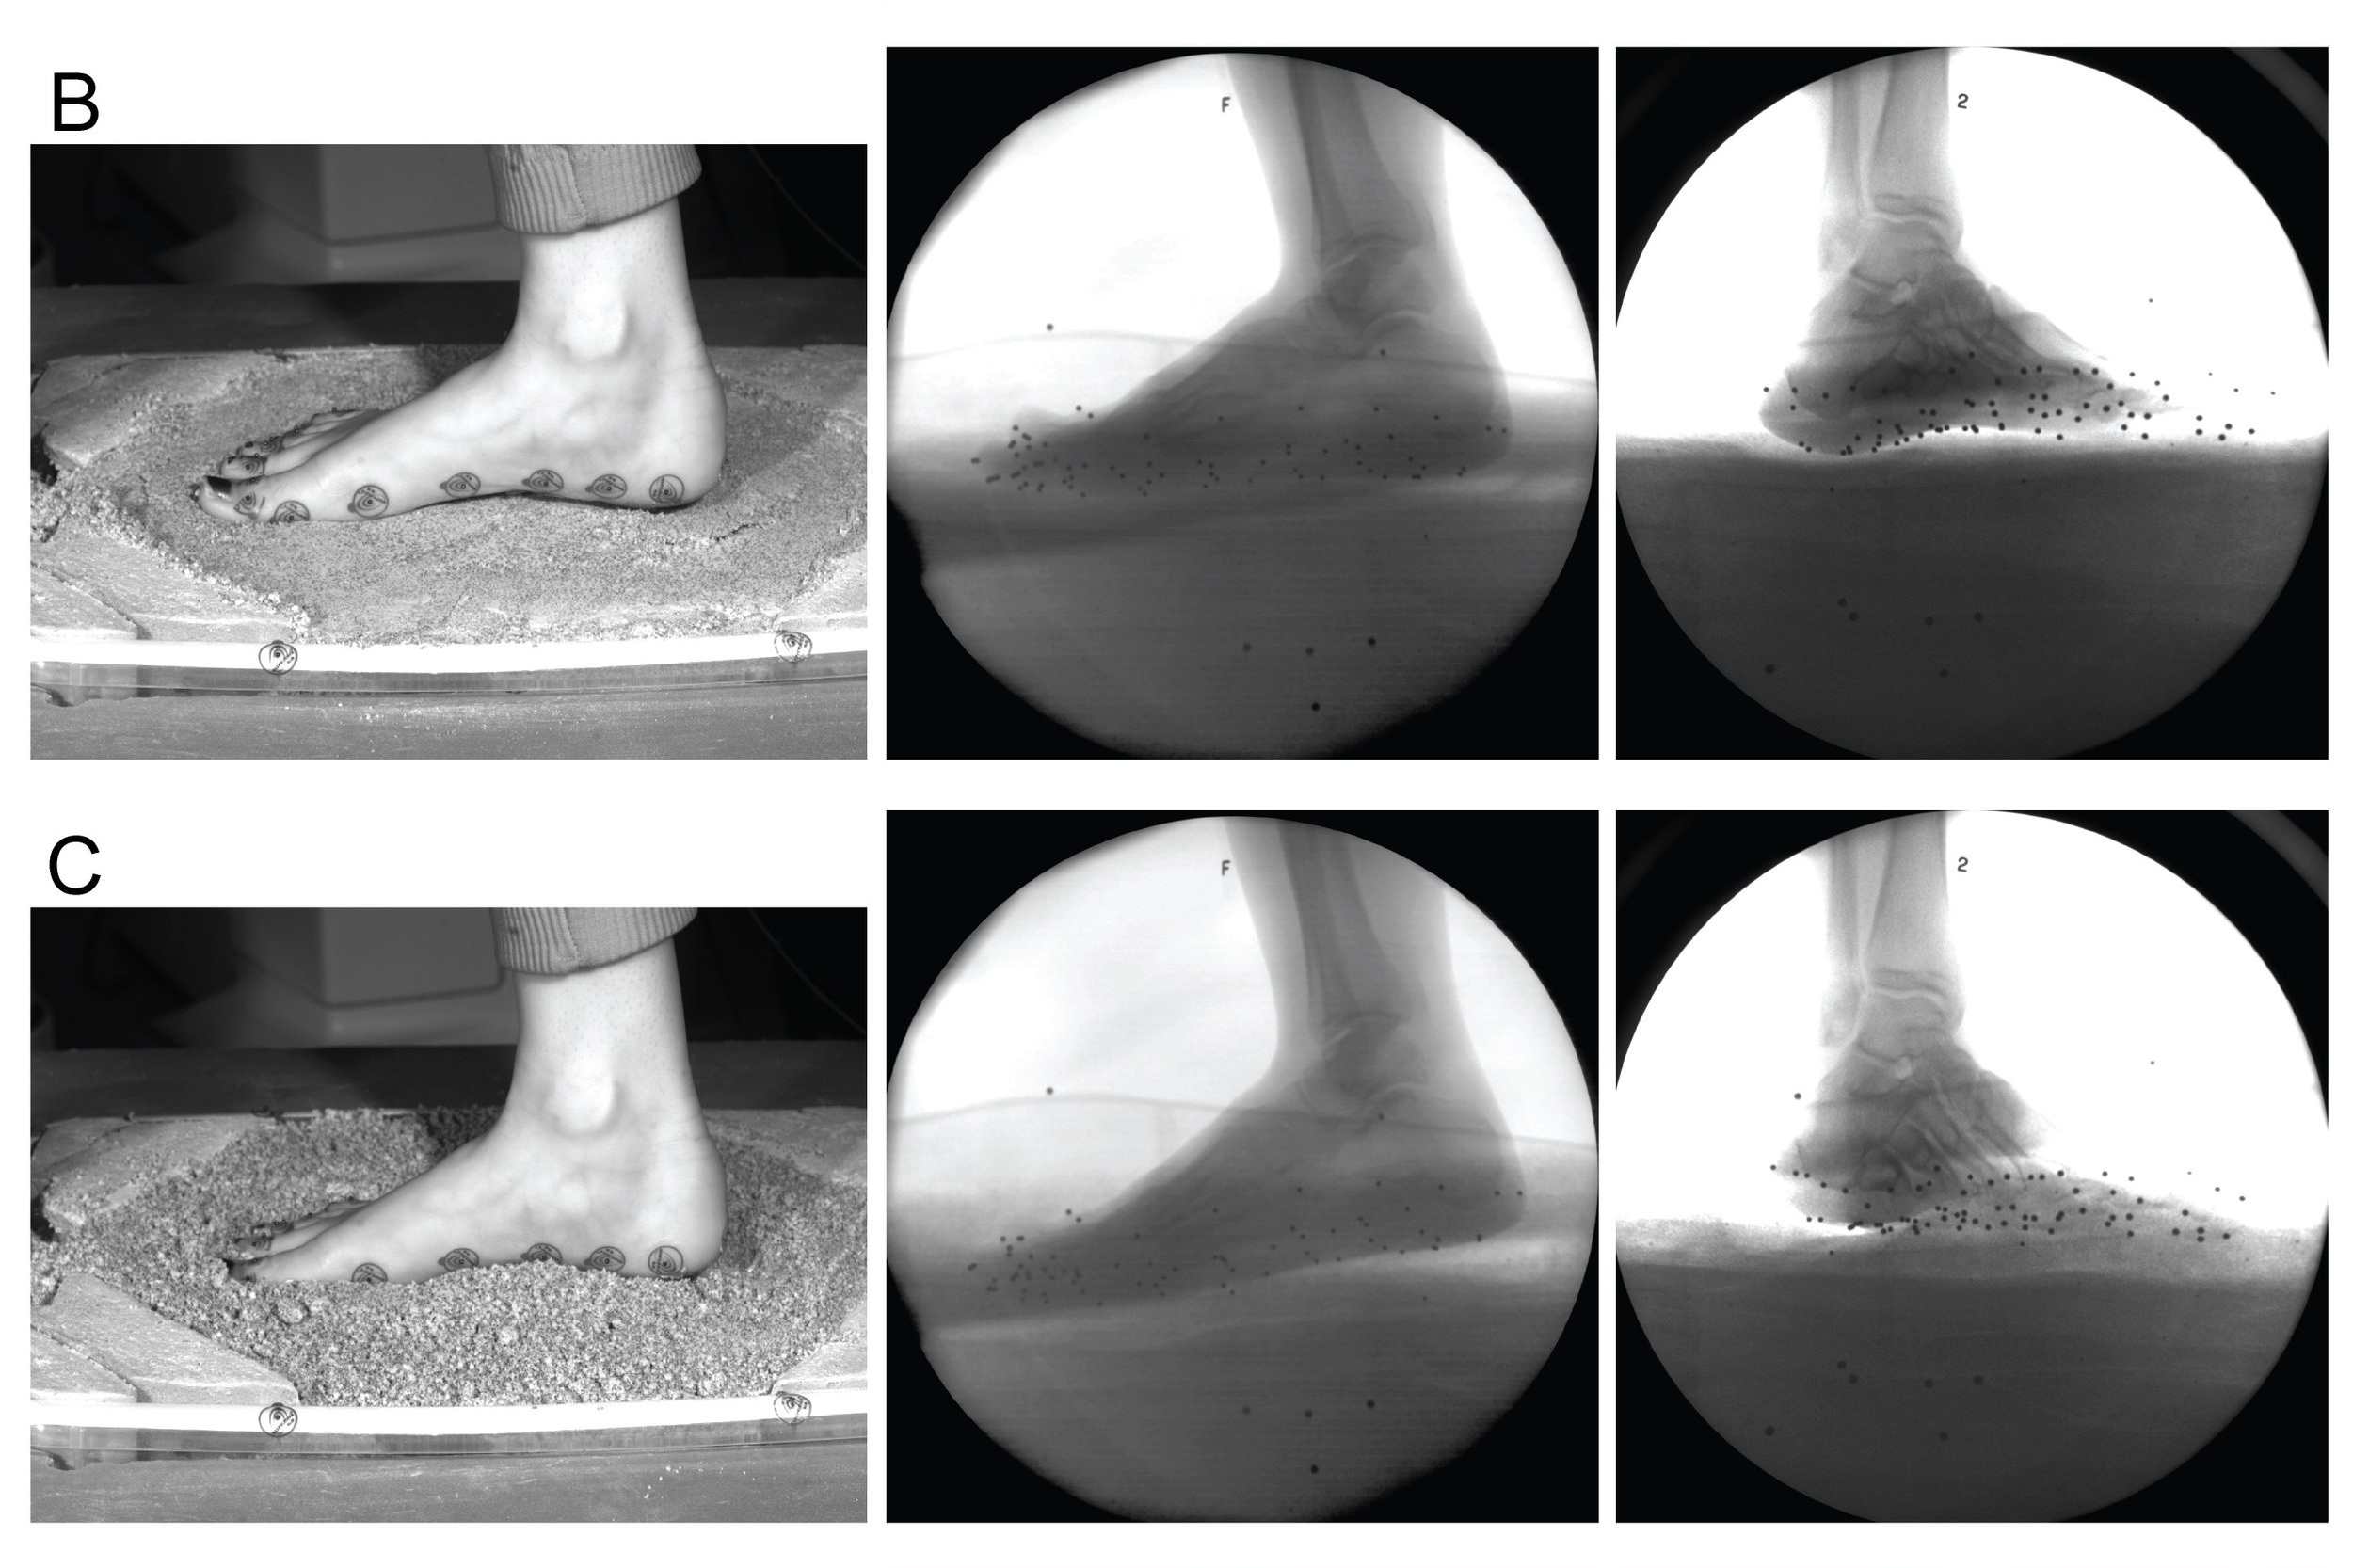

Our experimental research examines human anatomy and biomechanics, and develops methods for studying anatomy and function from the human fossil record.